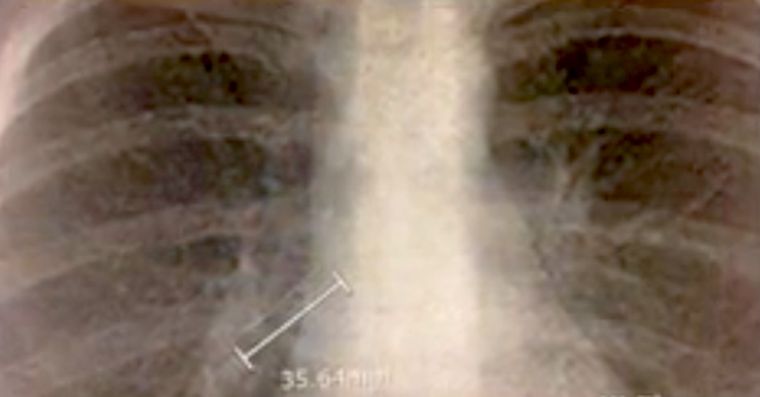

Todos imaginan la fiesta de graduación como algo casi mágico. Y de hecho lo es para muchas ymuchos adolescentes. Es el momento en que pueden despedirse de sus compañeros y pasar una noche inolvidable. Sin embargo, Kathleen Garvey, de la escuela Wellesley High, vivió una experiencia bastante desagradable. Ella se tragó un prendedor de 4 centímetros, el cual quedó alojado en los bronquios de la muchacha. Eso le provocó dificultades para respirar y le dio un buen susto. Mira cómo se desarrolló la historia:

Al instante comenzó a toser, aunque la fiesta siguió con total normalidad. Para asegurarse de que no era grave, Kathleen fue al médico al día siguiente. Los médicos no podían creer lo que tenía en sus pulmones…

Al instante, los doctores la prepararon para una cirugía y pudieron quitar el pendiente. Kathleen se siente muy afortunada.